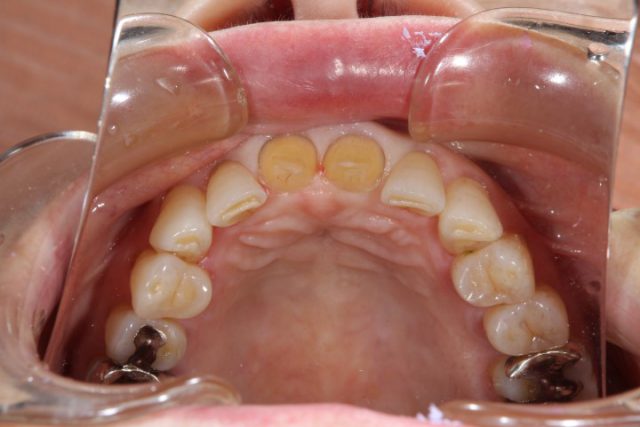

施術中

前歯の被せ物の取り替える場合はまわりの歯との色味をどこまで自然に合わせてくるかが重要になります。せっかく被せ物をやり直すからできるだけ白いものと思ってしまいそうですが、まわりの歯と色味が合わないと白くても違和感が出てきてしまいます。